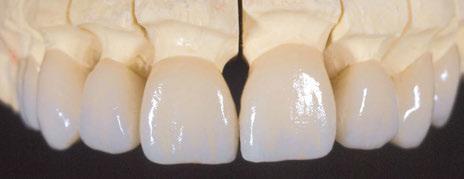

Presentamos el tratamiento rehabilitador de una paciente, realizado íntegramente en una sesión. Para este caso se ha utilizado un protocolo quirúrgico digital y guiado mediante la Plataforma de Planificación Bego Guide. Asimismo, se ha diseñado digitalmente una prótesis de carga inmediata atornillada e impresa con resina Bego VarseoSmile TriniQ®. Por lo tanto, se trata de un caso cuyo tratamiento precisa diferentes fases, pero efectuadas, todas ellas, el mismo día. De forma sencilla y cómoda para la paciente y el odontólogo, se ha obtenido una rehabilitación fija, funcional y estética. Palabras clave: Cirugía guiada, implantología oral guiada, cirugía sin colgajo, férula quirúrgica, rehabilitación fija maxilar, impresión digital, escáner intraoral, implantes dentales.

procediendo a realizar una solicitud de encargo a través de un formulario. Antes de 72 horas recibimos una propuesta terapéutica. En ella se facilitan vistas 3D detalladas, así como valoraciones y consideraciones a tener en cuenta durante el fresado y la inserción de los implantes (Figuras 9 a 19). Decidimos realizar extracción de todas las piezas remanentes, dada su nula viabilidad a corto-medio plazo y en Bego (a través del portal) proponen mantener 3 piezas (las más viables técnicamente) en cada arcada para proporcionar el anclaje óptimo de la

Figura 34. Rehabilitación superior impresa en resina Bego VarseoSmile TriniQ® lista para atornillar. Se han anulado de la oclusión aquellos implantes que no obtuvieron una estabilidad primaria superior a 35 N/cm2 Figura 31. Escaneado intraoral postcirugía. Figura 32. Rehabilitación recién impresa a través de impresora Varseo XS con resina Bego VarseoSmile TriniQ®. Figura 33. Ajuste pasivo entre aditamentos protésicos y la rehabilitación impresa.

aproximadamente una hora y media. Usamos resina Bego VarseoSmile TriniQ® para puentes definitivos. Aunque en este caso la vamos a usar para confeccionar unas prótesis fijas atornilladas provisionales de larga duración, dado al aumento de dimensión vertical que vamos a realizar a la paciente, de esta forma obtendremos una neuroprogramación de la ATM reinstaurando una Dimensión Vertical apropiada y mejorando la estética facial de la paciente. Excluimos de la carga aquellos implantes que no obtuvieron una estabilidad primaria superior a 35 N/ cm2. El material permite la realización de una carga inmediata en material definitivo en puentes (Figuras 31 a 38).

Decidimos realizar una prótesis impresa ya que permite trabajar bajo el concepto «chairside», es decir, de ser necesario, desde la misma consulta, con el paciente en ella (en nuestro caso descansando desde la sala de recuperación), sin necesidad de intermediarios, se puede confeccionar una prótesis completamente personalizada con una adaptación y pasividad total. Asimismo parece que la impresión 3D produce coronas permanentes con una precisión dimensional superior (12).